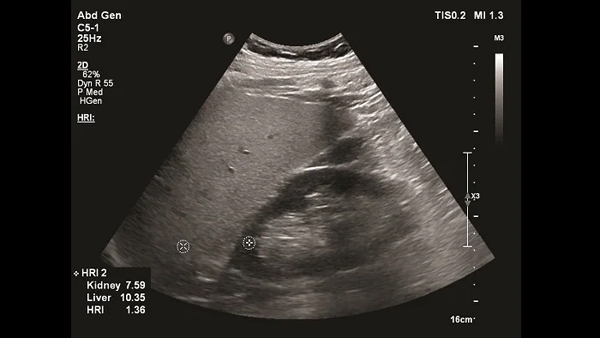

計算能力の向上で超音波診断装置が進化、脂肪を定量化して脂肪肝を早期発見日経クロステック xTECH。

キヤノンメディカルシステムズ、『肝臓の脂肪量の汎用超音波画像診断装置による正確な測定法の確立の検討』に関する国内多施設臨床研究をサポート映像情報Medical。

メディカルwatch » Blog Archive » 『肝臓の脂肪量の汎用超音波画像診断 装置による正確な測定法の確立の検討』に関する国内多施設臨床研究に関して。